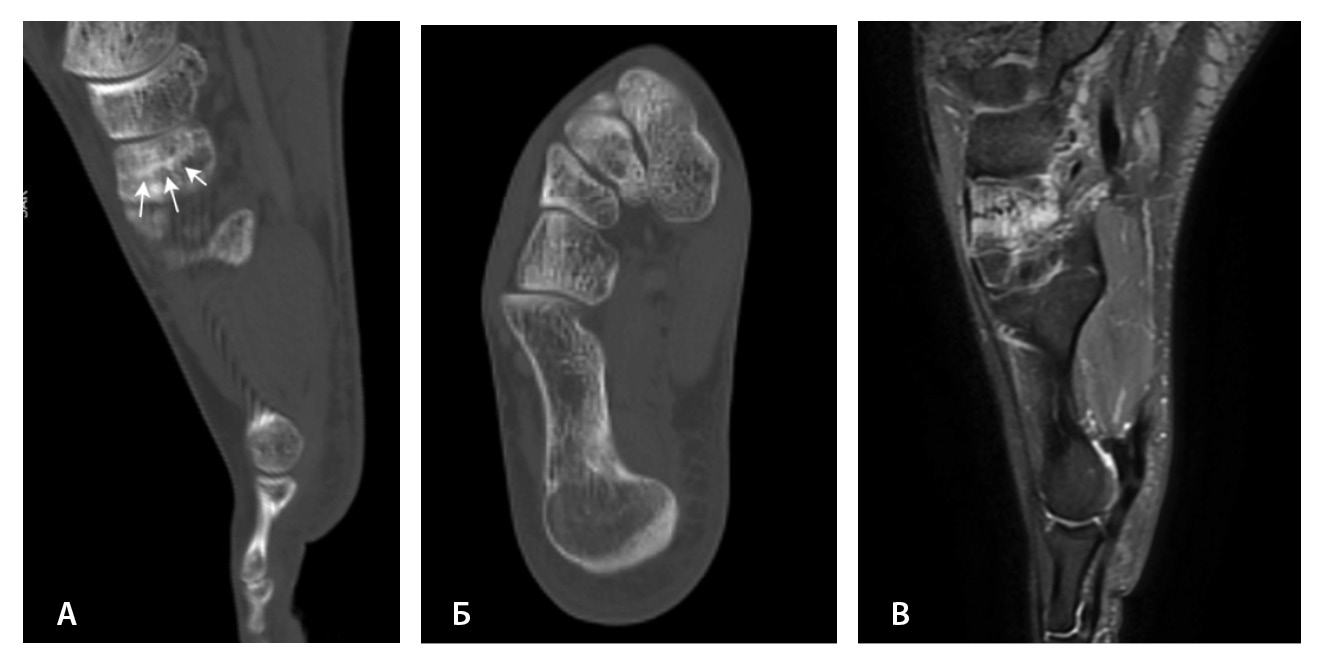

КТ – метод выбора при высокоэнергетической травме конечностей в предоперационном периоде (переломы пилона, многооскольчатые переломы костей стопы), так как позволяет с максимальной точностью по сравнению с другими методами лучевой диагностики определить количество, положение, характер расхождения, угловое и многоплоскостное смещение костных фрагментов, уточнить тип перелома и распространение линий перелома на суставные поверхности и область тарзального синуса [19, 23, 44]. При многооскольчатых переломах пяточной кости оценивают сохранность опоры таранной кости, так как через нее зачастую проводят металлоконструкции при репозиции костных отломков, измеряют передне-задний размер пяточной кости, ее вальгусное или варусное отклонение [23].

Переломы без смещения фрагментов, а также краевые и авульсионные переломы не всегда четко визуализируются на рентгенограммах из-за суперпозиции теней, наличия фиксирующих шин и гипсовых повязок, которые накладываются на зону интереса. При клинических признаках перелома и рентгеннегативной картине у таких пациентов КТ имеет большую диагностическую значимость (рис. 2).

Рис. 2. Рентгеннегативный перелом дистального метадиафиза большеберцовой кости 2-го типа по Солтеру – Харрису (стрелки) у мальчика 11 лет: А, Б – рентгенография; В – компьютерная томография (КТ), корональная плоскость; Г – КТ, сагиттальная плоскость; Д – КТ, аксиальная плоскость

Переломы таранной кости, в том числе с распространением линии перелома на подтаранный сустав, трудно обнаружить на рентгенограммах, однако КТ может помочь в их диагностике. M. Avci и соавт. выявили 30% чувствительность и 98% специфичность рентгенографии при переломах таранной кости [44]. J.D. Dale и соавт. установили, что рентгенография имеет более низкую чувствительность (78%) для обнаружения и локализации переломов таранной кости по сравнению с КТ (99%) [46]. Следует оценивать распространение линии перелома и ее близость к медиальной поверхности пяточной кости. Вовлечение пазухи предплюсны увеличивает риск развития остеонекроза и нестабильности в подтаранном суставе [23].